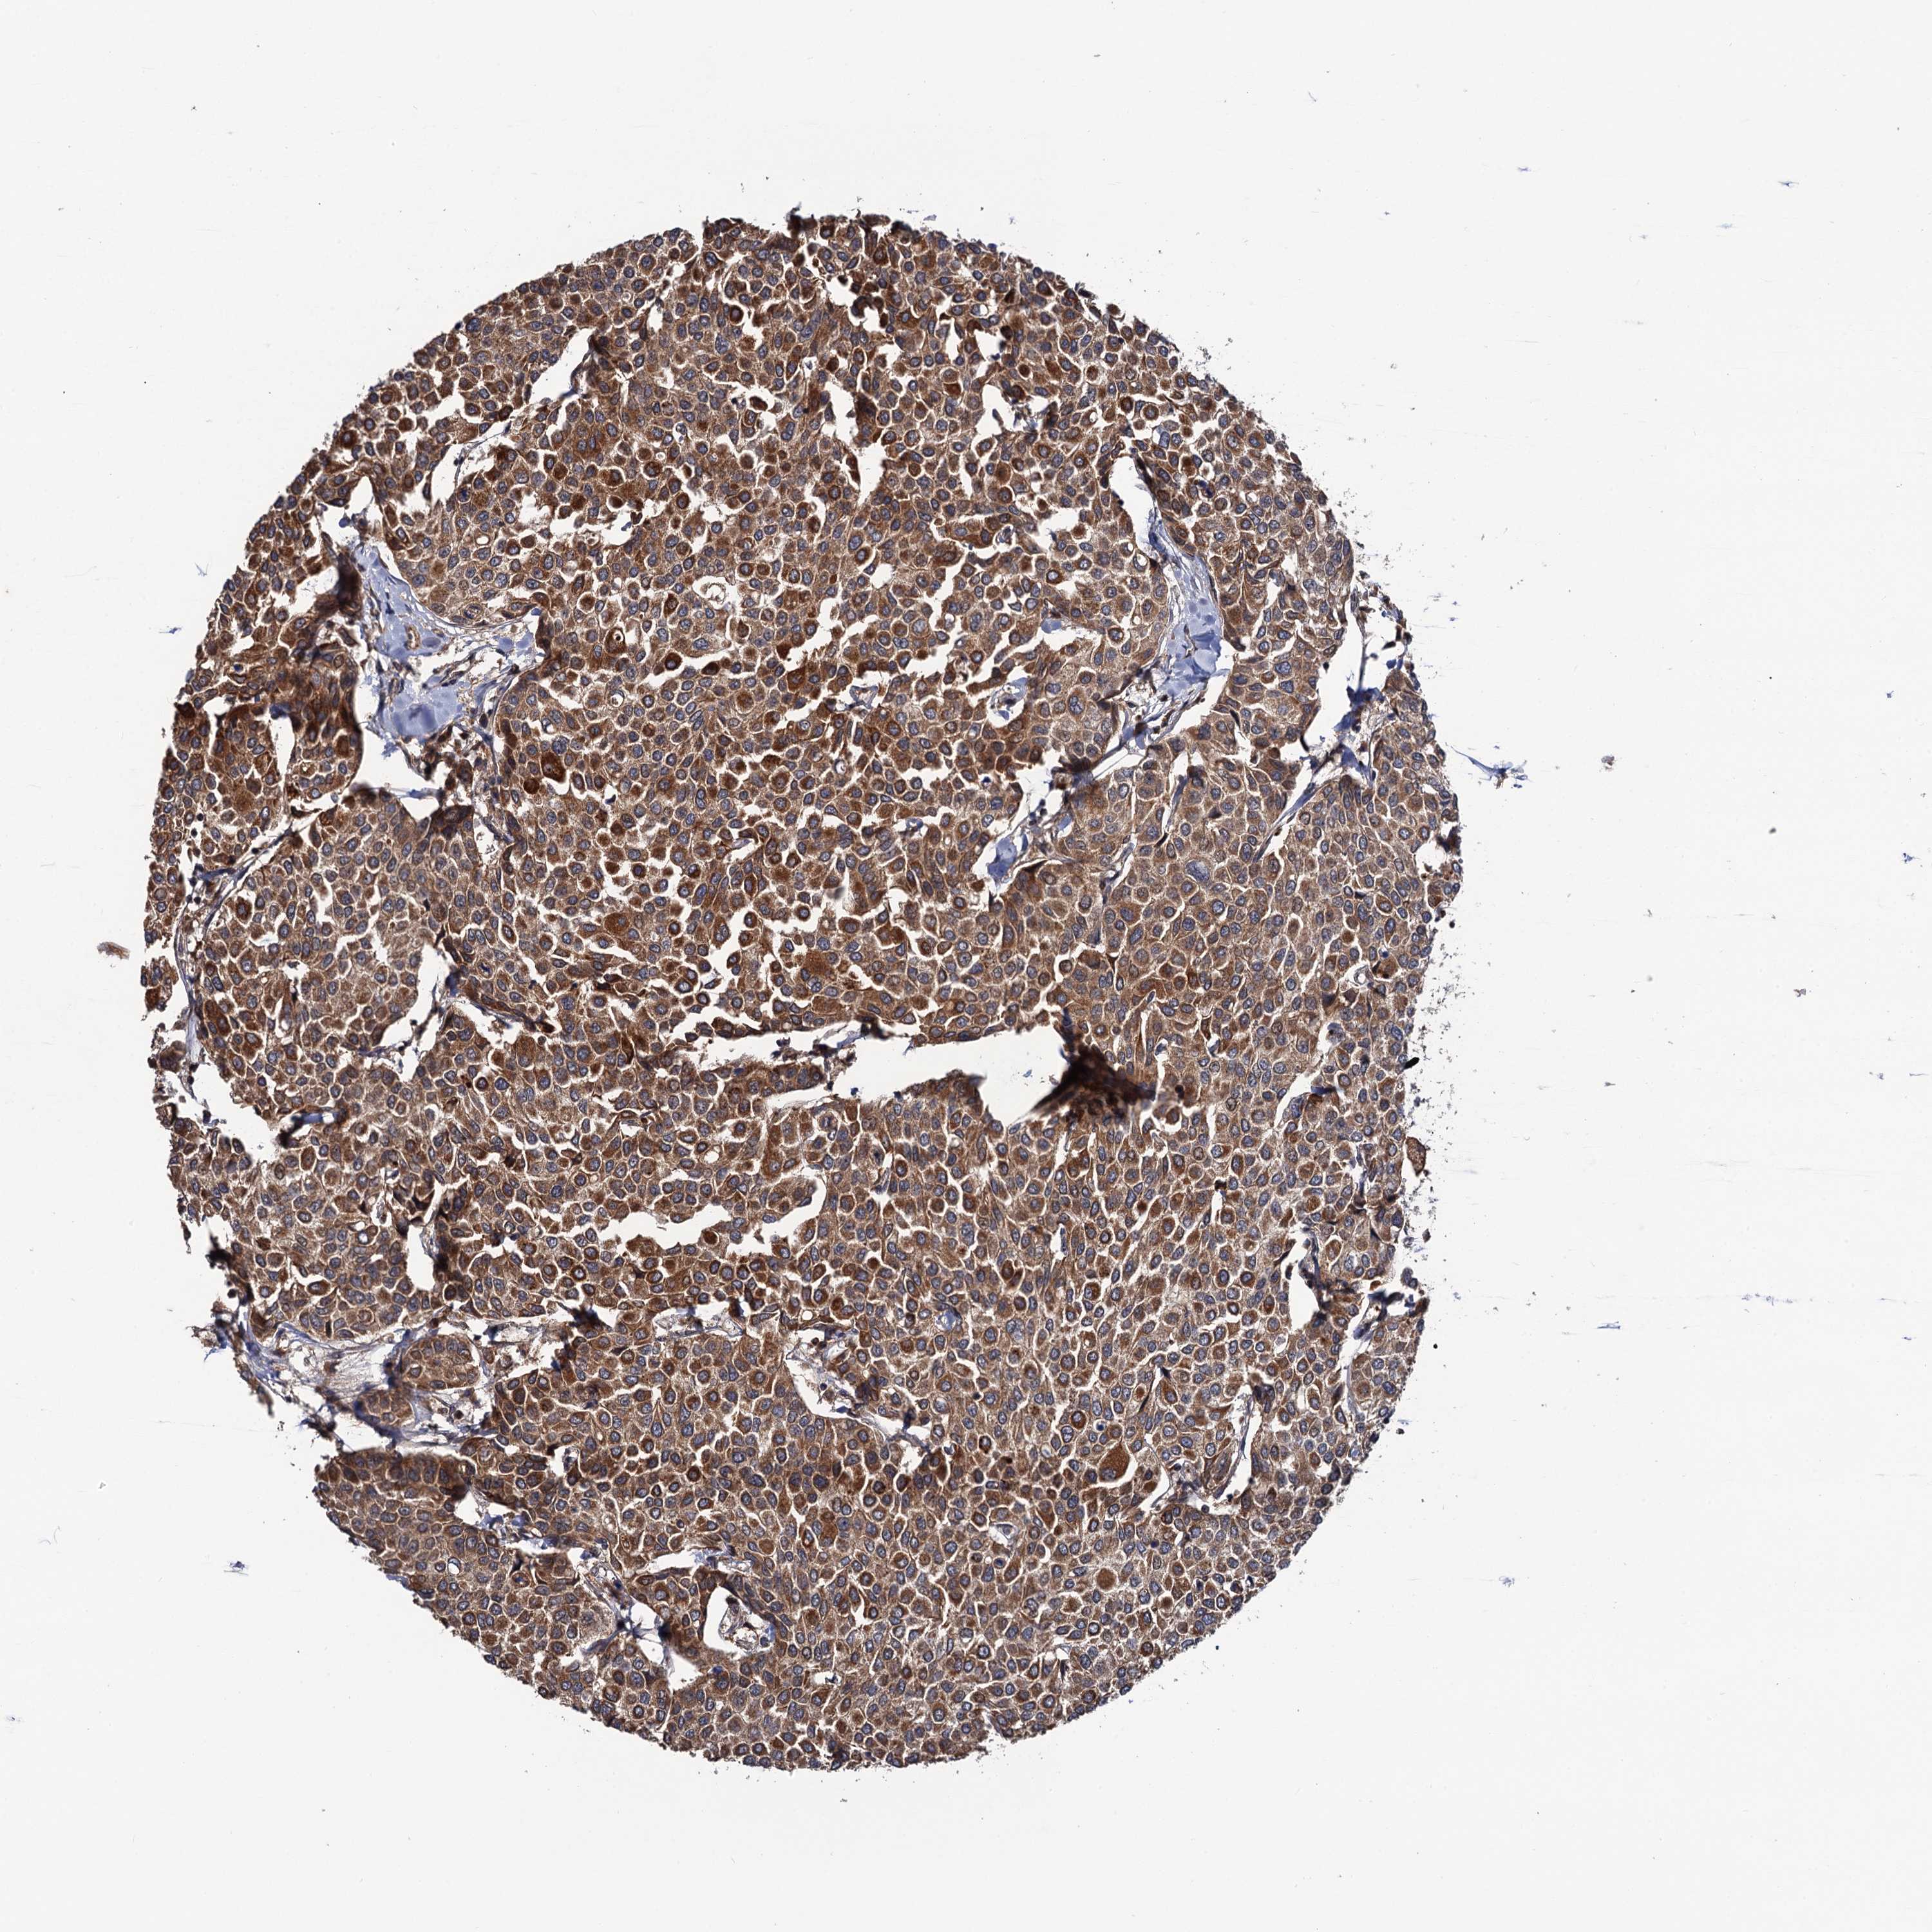

BRCA TCGA BRCA VALIDATION PROTEIN EXPRESSION